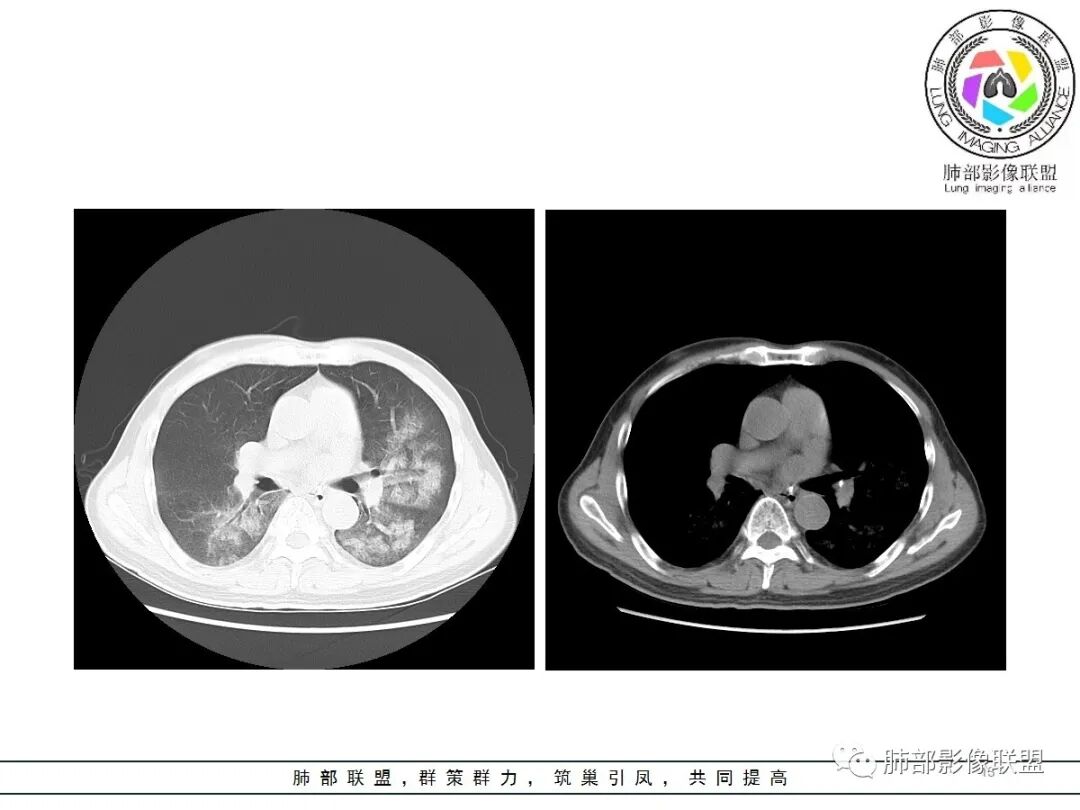

影像:双肺对称性中内带为主分布磨玻璃影,实变不明显。无胸水及小叶间隔增厚。

病史中D2聚体明显升高,影像:双肺对称性中内带为主分布磨玻璃影,有坠积感,实变不明显,胸膜下回避。无胸水及小叶间隔增厚;肺水肿?感染?建议CTPA检查除外肺栓。

CT示双肺中内带多发斑片状磨玻璃影,沿支气管血管束分布,边界模糊,部分支气管壁增厚。定位气道来源的病变,考虑非典型病原体感染,鹦鹉热可能。

男,65,咳嗽、发热1天,黄粘痰,痰中带血。饲养鹦鹉,新冠疫苗第二针后,本地有新冠病例。血像高。胸部CT:双肺中内带多发斑片样磨玻璃影,边缘不清,沿支气管血管束分布,左肺重,细网络,小叶内间隔增厚,支气管充气征。诊断:肺门为中心两侧大概对称GGO,首先考虑DAH(血管炎)?不典型病原体感染,鹦鹉热、病毒待排。鉴别肺水肿、PCP等。

影像是符合肺水肿

已有临床资料可以排除心源性和肾源性水肿

肺水肿影像表现

1.间质性肺水肿:小叶间隔增厚,尚光滑,支气管血管束增粗,肺血管影模糊,胸膜或叶间裂增厚,肺内有磨玻璃密度影,常有重力分布趋势。

2.肺泡性肺水肿 :

(1)中央型分布:以肺门为中心,两肺中内带对称分布的大片状实变,称为“蝶翼征”。常见于心源性及肾源性肺水肿患者。也可表现为磨玻璃密度病灶,弥漫性分布或以小叶中心性分布。

(2)弥漫型肺水肿:弥漫分布于两肺内的多发斑片状磨玻璃密度及实变影,大小和密度不等,可融合成大片状阴影,可见空气支气管征。